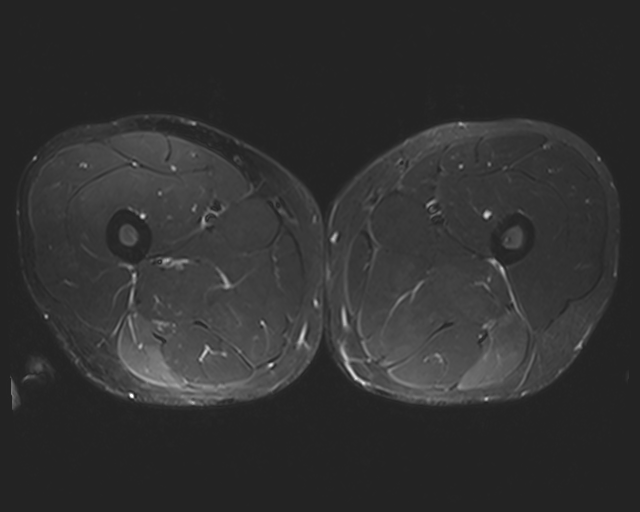

We chose the Fusion_Gate method for our application-grounded evaluation because it achieved the highest scores, albeit modest, in our functionally-grounded evaluation. Figure 7 presents all five distal myopathy cases side by side with their reference masks and the corresponding Fusion_Gate saliency maps, providing a direct visual comparison of true pathology versus model-identified regions. After converting each HCP’s annotations into binary masks, we computed the coherence between those masks and the Fusion_Gate saliency maps (Table 7). The large spread in RMA and RRA values demonstrates that even minor discrepancies in the ground truth mask can dramatically alter coherence scores, emphasizing the critical need for highly accurate, consensus ground truth annotations when using coherence as an interpretability metric. We then assessed each HCP’s overall annotation accuracy by RMA¯\overline{\mathrm{RMA}}over¯ start_ARG roman_RMA end_ARG and RRA¯\overline{\mathrm{RRA}}over¯ start_ARG roman_RRA end_ARG against the reference masks (first column of Table 8). RMA¯\overline{\mathrm{RMA}}over¯ start_ARG roman_RMA end_ARG indicates that HCPs reliably identify the general signal alteration regions, but their consistently lower RRA¯\overline{\mathrm{RRA}}over¯ start_ARG roman_RRA end_ARG confirms they lack the fine-grained precision of the expert in isolating the most critical subregions. Notably, when we compare these human baselines to the Fusion_Gate’s mean coherence scores (Table 5), the method’s RRA¯\overline{\mathrm{RRA}}over¯ start_ARG roman_RRA end_ARG surpasses that of all but two HCPs. In other words, the attention mechanism could faithfully highlights the single most important pixel than most individual annotators. Lastly, the comparatively low RMA¯\overline{\mathrm{RMA}}over¯ start_ARG roman_RMA end_ARG and RRA¯\overline{\mathrm{RRA}}over¯ start_ARG roman_RRA end_ARG values in the second column of Table 8, which quantify how well the Fusion_Gate saliency maps align with each HCP’s own mask, reveal that even our best interpretability method still falls short of expert-level delineation. In other words, although attention-based saliency can highlight broadly relevant regions, it does not yet match the clinical precision of HCPs’ annotators. This gap underscores that, despite promising advances, more work is needed before automated explanations can achieve the same fidelity as experienced radiologists.

Refer to caption

(a) Image 1

(b) Ground truth Mask 1

(c) Saliency Map 1

(d) Image 2

(e) Ground truth Mask 2

(f) Saliency Map 2

(g) Image 3

(h) Ground truth Mask 3

(i) Saliency Map 3

(j) Image 4

(k) Ground truth Mask 4

(l) Saliency Map 4

(m) Image 5

(n) Ground truth Mask 5

(o) Saliency Map 5

Figure 7: Image instances of the distal myopathy dataset with their corresponding reference masks and saliency maps.